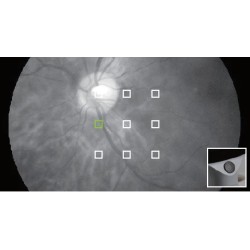

9 cibles de fixation

Avec 9 cibles de fixation, l’OPT-RNM61 couvre un champ de vision de 85° du fond d'œil et prend en charge l'examen des lésions périphériques précoces du fond d'œil. Avec un champ de vision de 45°, une seule image du fond d'œil central peut être prise pour répondre aux besoins du dépistage de la maladie du fond d'œil.